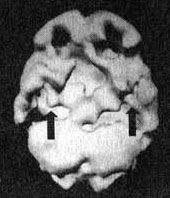

Мозг Нэнси - последствия двух инсультов

Трехмерное изображение поверхности, вид сверху

Трехмерное изображение поверхности, вид справа